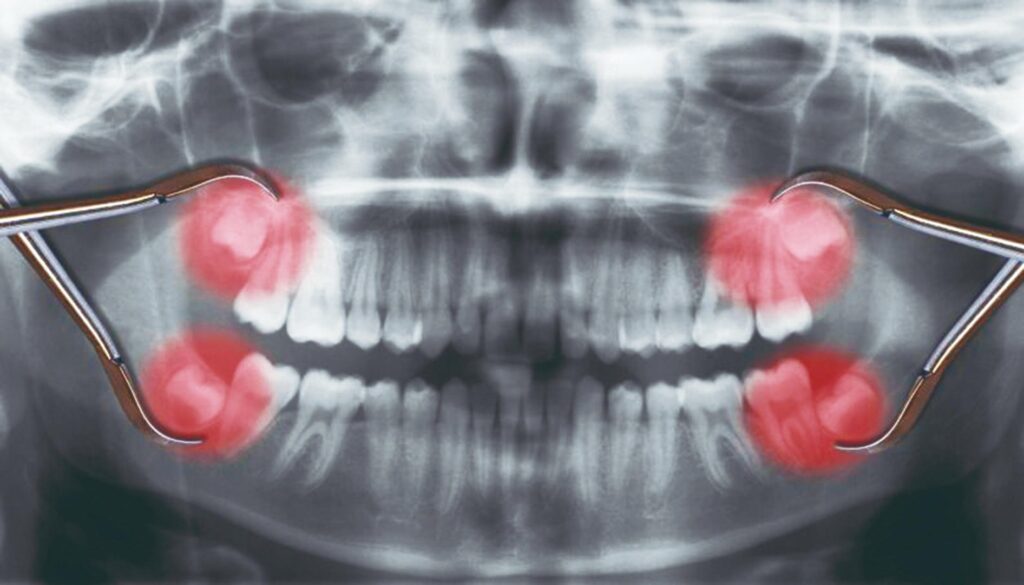

Todo mundo tem quatro sisos?

Não. Há pessoas que podem não apresentar nenhum deles ou todos. Em alguns casos, o dente até pode estar ali – mas a erupção não ocorre. Mas, na maioria das vezes, surgem os quatro sisos mesmo: dois superiores e dois inferiores.